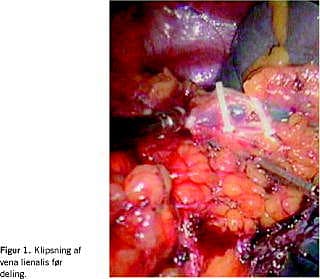

OS blev foretaget af forskellige operatører sædvanligvis via venstresidig subkostal incision. Alle LS blev foretaget af samme operatør. Patienten lå i højre sideleje. Der blev anlagt to 10-12 mm-porte og to 5 mm-porte. Nedre miltpol blev frilagt ved deling af det splenokoliske ligament. Der blev herefter åbnet til lille sæk, og vasa brevia blev delt fra ventrikelsiden. Efterfølgende blev arteria lienalis påsat klips uden at dele den, således at blodtilførslen til milten blev standset, mens tilbageløb via vena lienalis stadig var muligt. Herved opnåedes skrumpning af milten, hvilket lettede den videre dissektion samt minimerede en eventuel blødning fra milten. Den øvre miltpol blev dissekeret fri for adhærencer mod diaphragma og retroperitoneum. Milthilus blev frilagt, og karrene blev delt enkeltvis (Figur 1 ). Milten blev placeret i en endobag, fragmenteret og fjernet gennem en af 12 mm-portene, som inden var blevet udvidet.